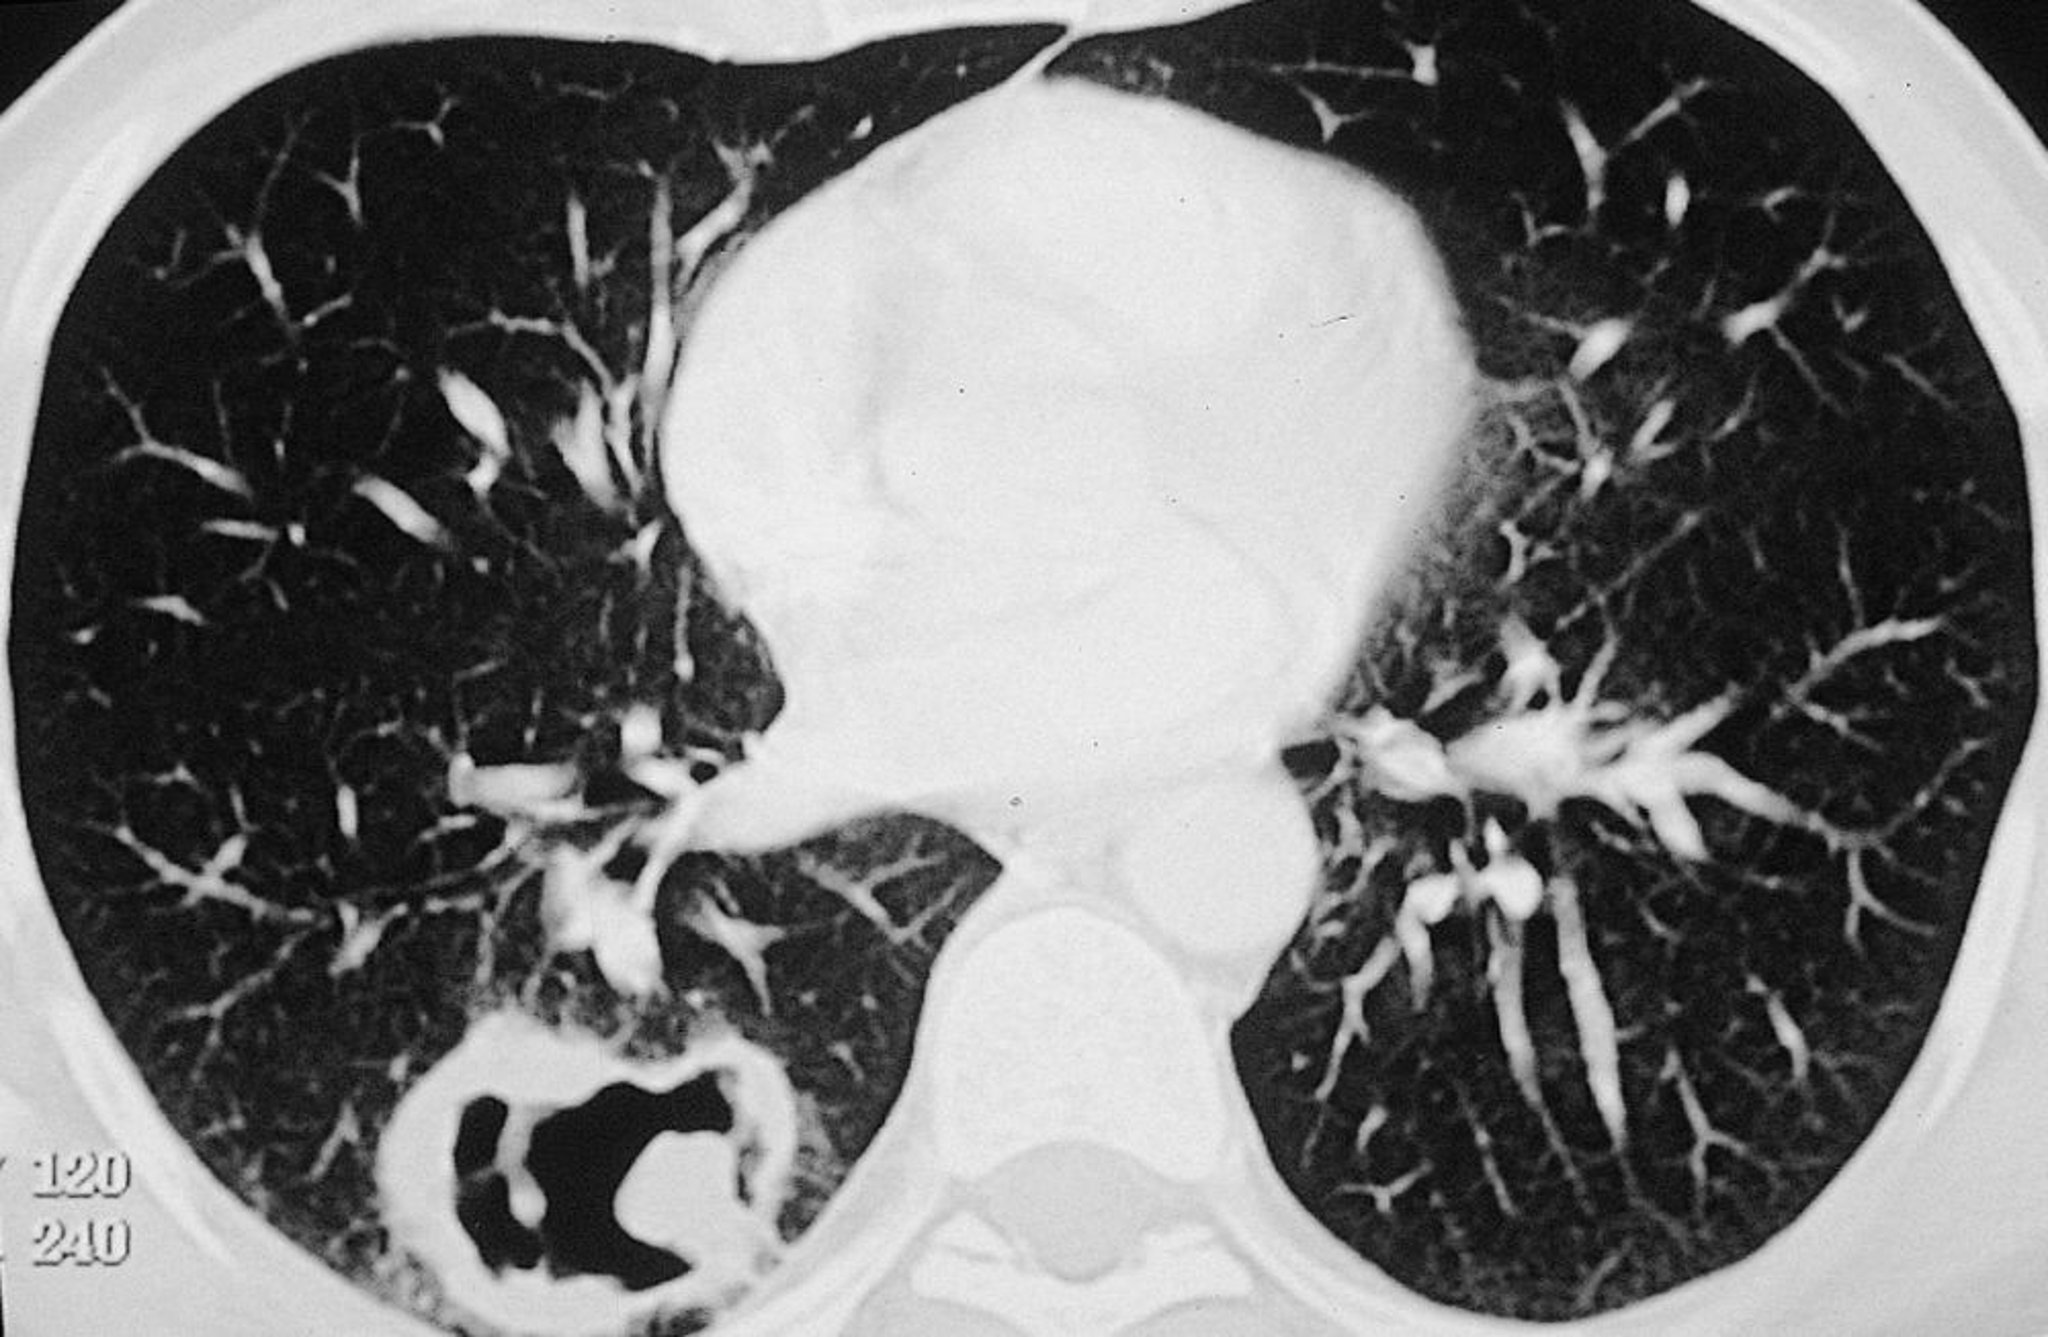

Lesión cavitaria grande en el pulmón derecho en un paciente con granulomatosis con poliangeítis.